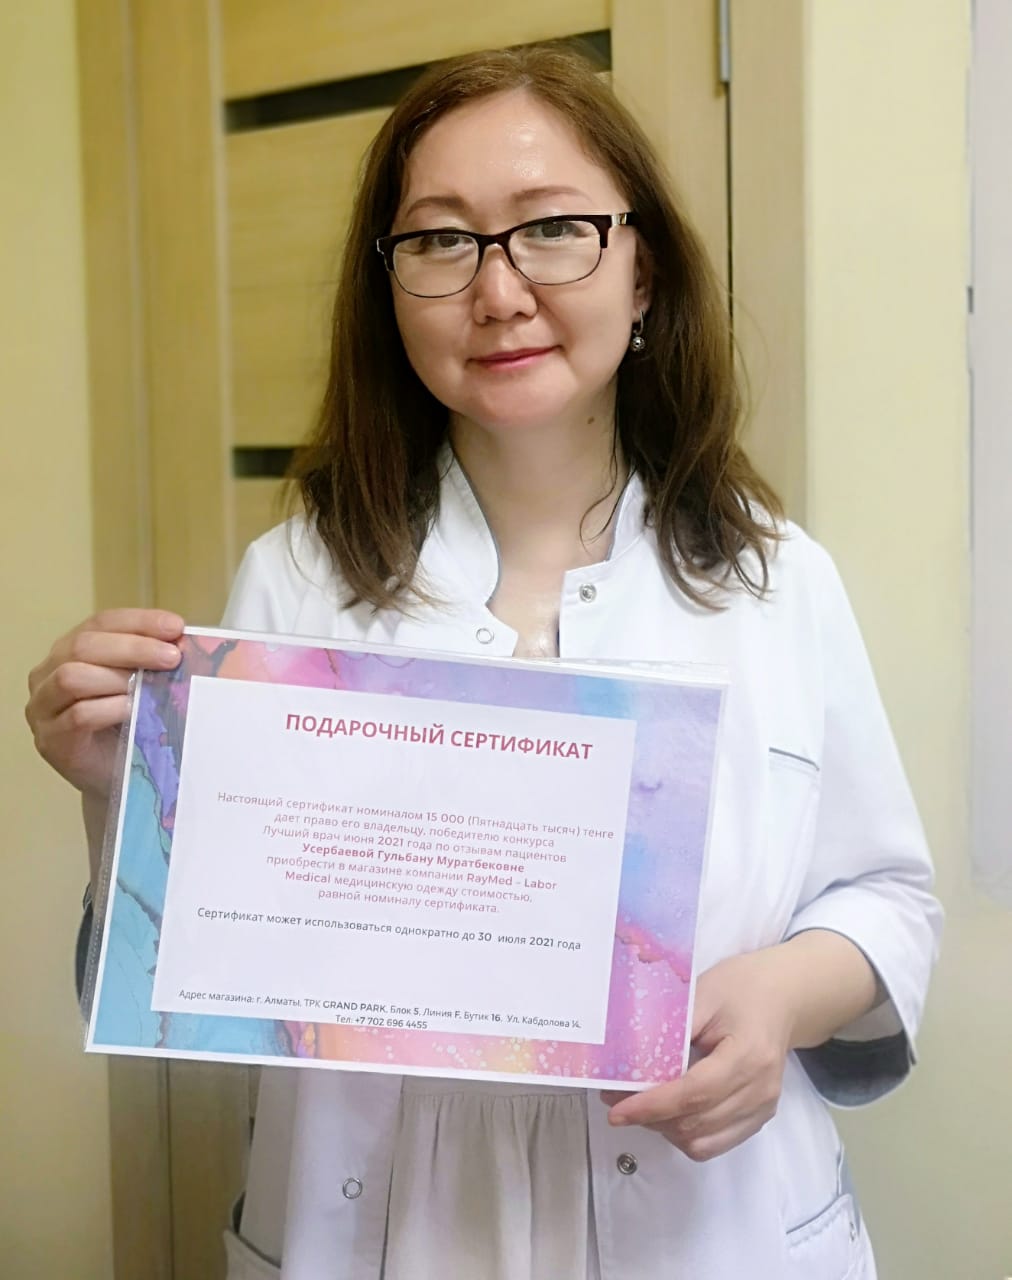

Лучший врач месяца по отзывам пациентов - ревматолог Гульбану Муратбековна Усербаева

Лучший врач месяца по отзывам пациентов - ревматолог Гульбану Муратбековна УсербаеваЛучшим врачом первого летнего месяца пользователи TopDoc.kz выбрали ревматолога с 26-летним стажем Усербаеву Гульбану Муратбековну. Врач Гульбану Муратбековна, кандидат медицинских наук, занимается лечением заболеваний соединительной ткани - суставов, кровеносных сосудов, кожи. Помогает при артрозе и артрите, подагре, остеопорозе, гранулематозе, васкулите и др., будучи доцентом кафедры Гульбану Усербаева всегда в курсе новейших достижений медицинской науки в своей области.